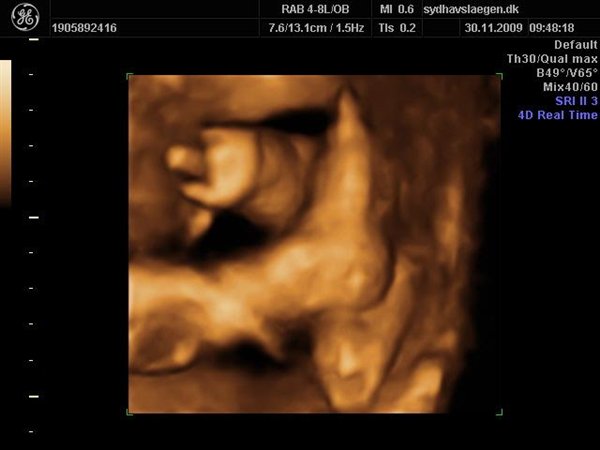

Da jeg snakkede med hende i dag sagde hun at fra uge 27 til og med uge 31 var det bedste tidspunkt at få det gjort....

Vi skal give 1400 kr for 45 minutters total gennem scanning, hvor hun fortæller, undersøger babyen fra top til tå, laver vægtskøn også får vi billeder og dvd med hjem.... Og ja det er da mange penge, men min forlovede har haft en masse vikar timer den her mdr, også sagde han at han syntes vi skulle bruge de penge på noget vi normalt ikke ville have gjort. Han sagde egentlig at jeg kunne gå ud og shoppe for dem, men jeg har termin om ti uger, så gider ærlig talt ikke bruge penge på nyt graviditets tøj, så hellere det her som vi egentlig havde valgt fra pga prisen, men som vi begge to rigtig gerne vil....